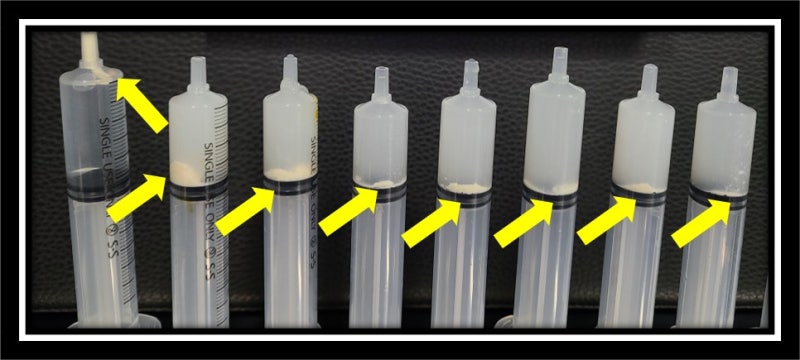

사진과 같이 석회분쇄흡입술을 시행하여 많은 양의 석회를 제거하였습니다.